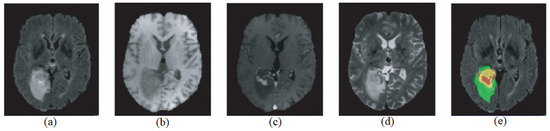

4.6. Qualitative Analysis